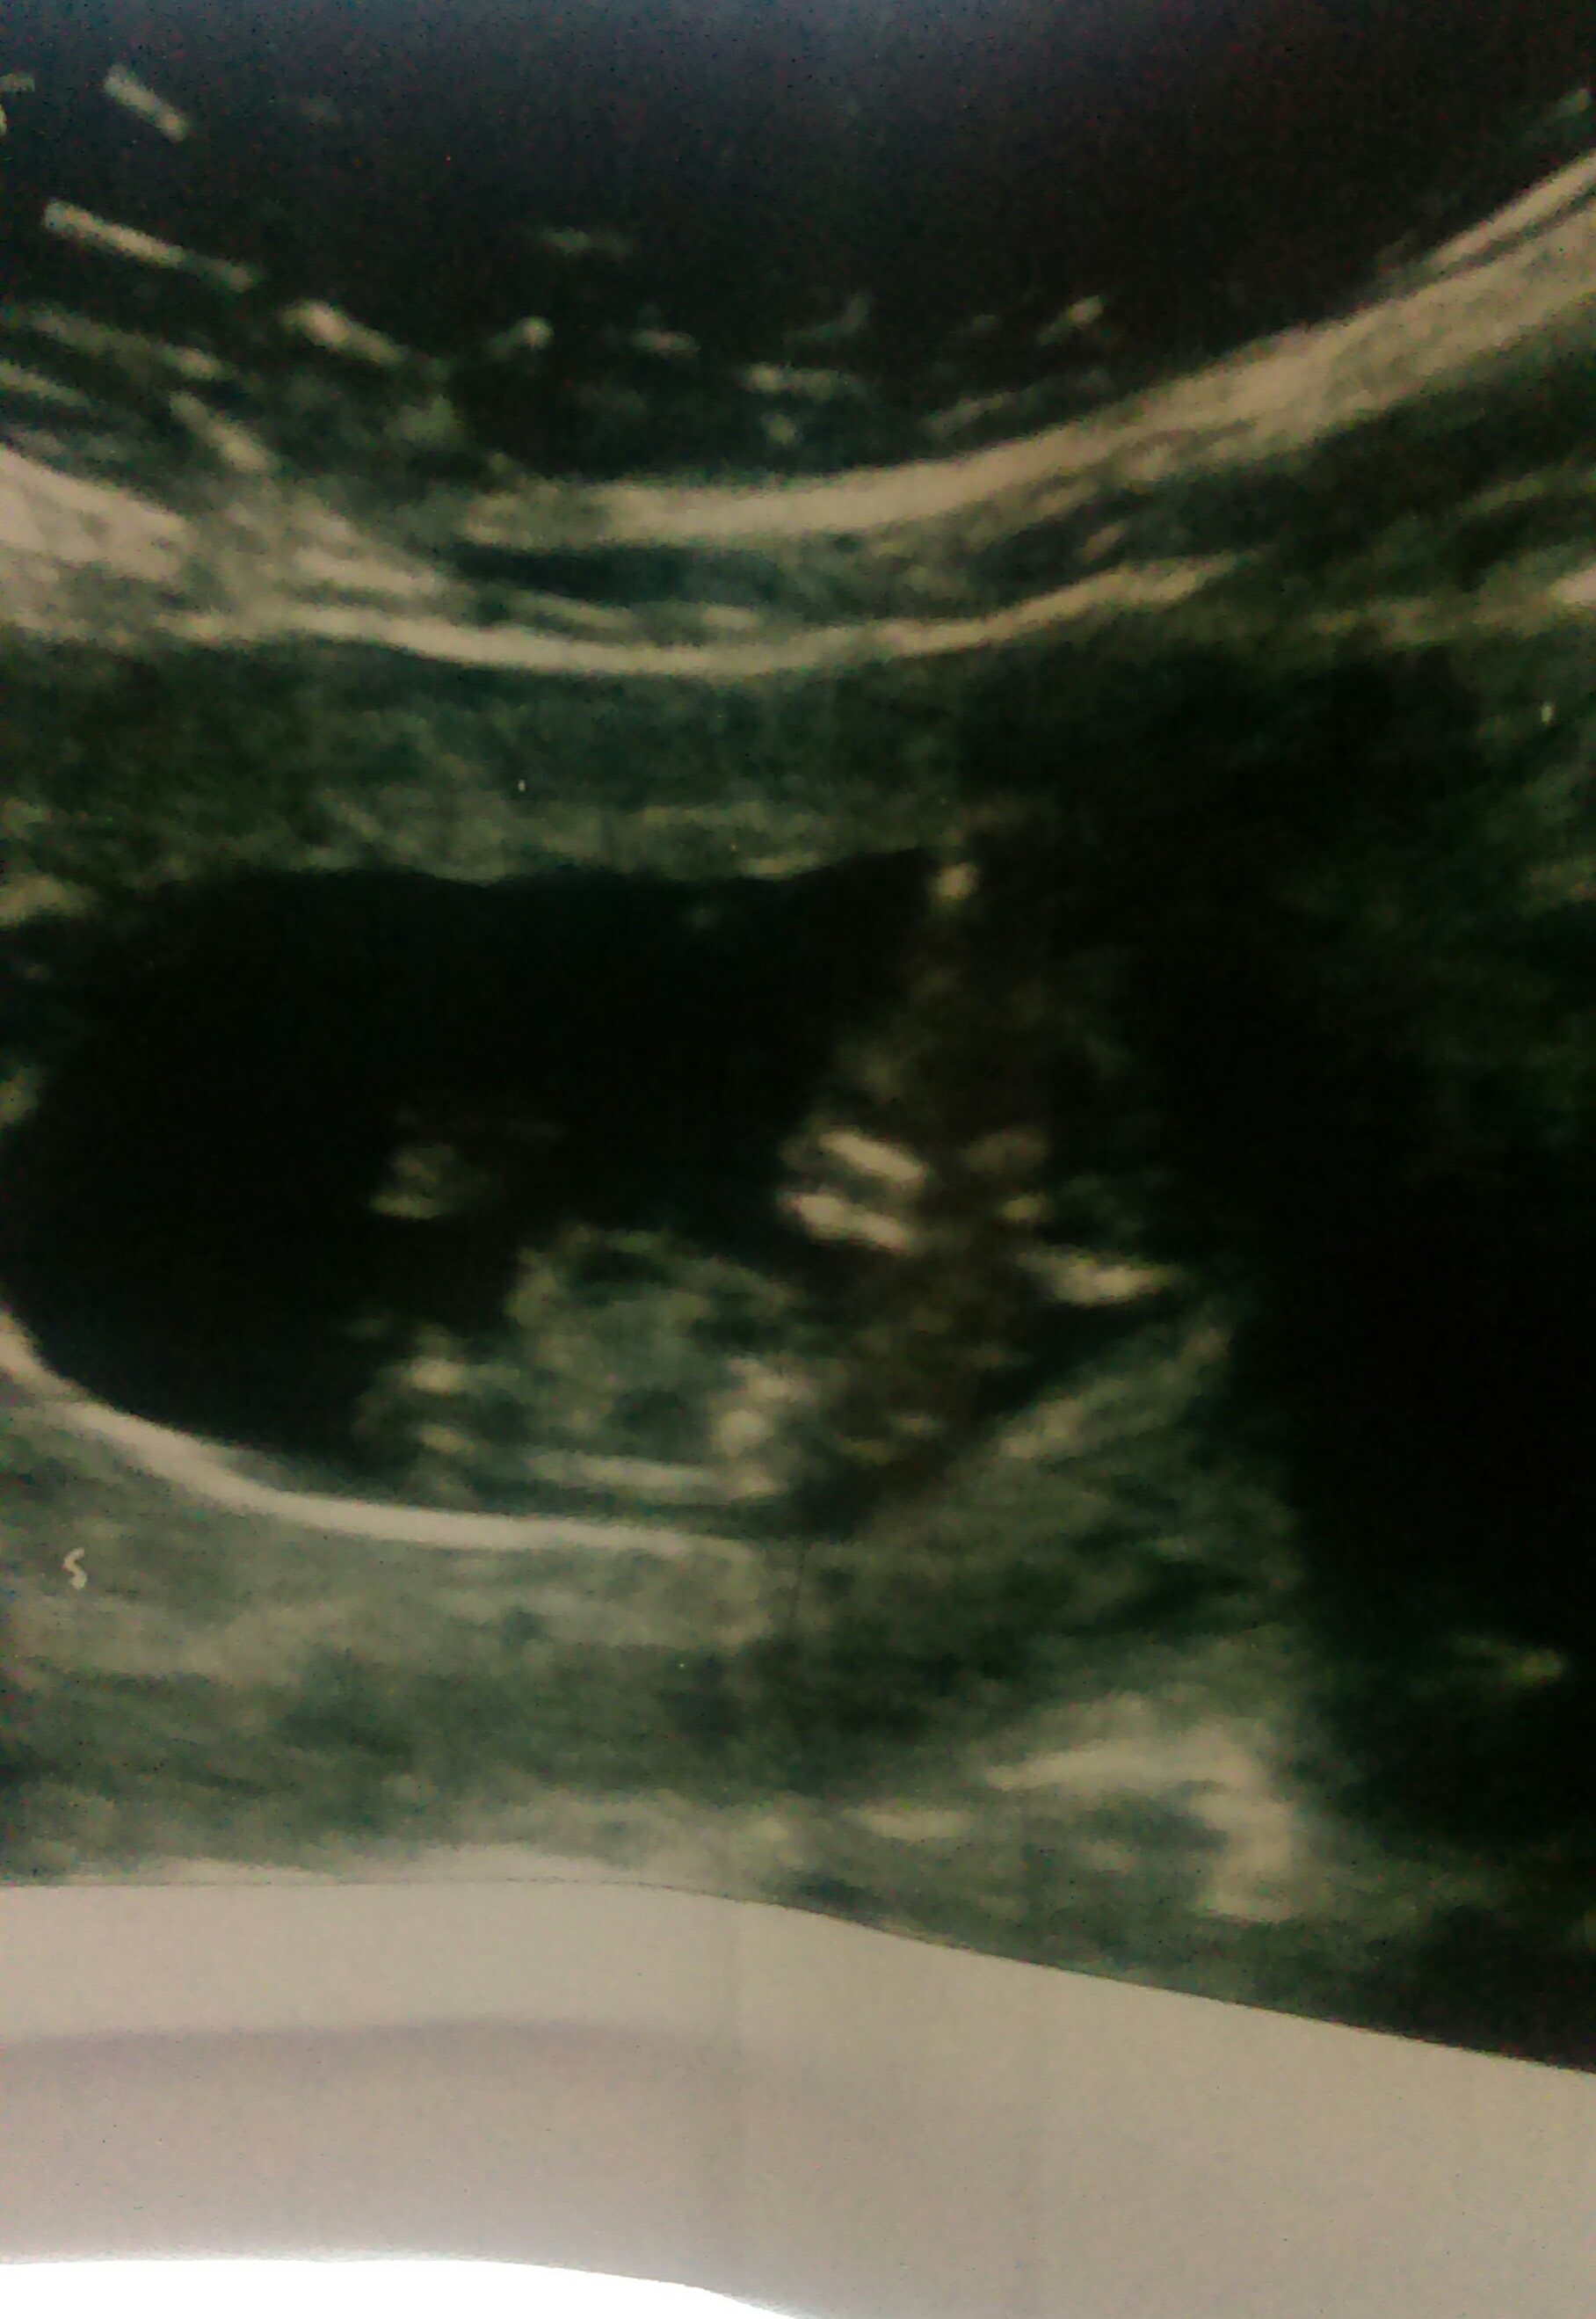

Attachment 29021

Maybe girl? What exact gestation was this? Measuring ahead or behind at all?

Very hard to see. Sorry!